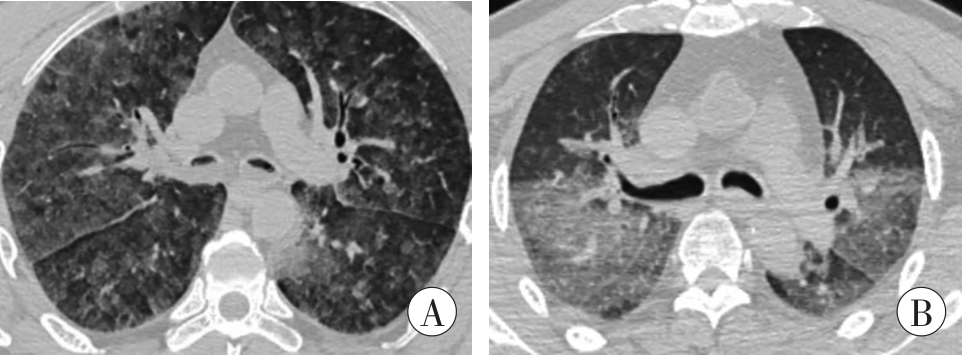

结果

溺死者死后影像可见呼吸道较多积液、肺部呈弥漫性较均匀的毛玻璃样改变;溺死者鼻窦(上颌窦及蝶窦)内积液量为(10.24±4.70) mL,对照组量为(2.02±2.45) mL;溺死者鼻窦内积液、左心房血液、胃内容物CT均值分别为(15.91±17.20)、(52.57±9.24)、(10.33±12.81) HU,较非溺死者低(P<0.05)。

Results

The postmortem CT of drowning showed the more fluid in respiratory tract than the non-drowning, and ground-glass opacities in the lung. The statistical volume of fluid in the sinus (maxillary sinus and sphenoid sinus) was (10.24±4.70) mL in drowning cases and (2.02±2.45) mL in non-drowning cases. The average CT value of fluid in the sinus, left atrial blood and gastric contents in drowning cases were (15.91±17.20), (52.57±9.24) and (10.33±12.81) HU, respectively, which were lower than those in non-drowning cases (P<0.05).